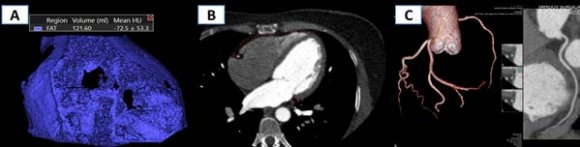

The area of EAT was calculated at the basal level of the ventricles of the heart along the short axis, as well as the area of adipose tissue of the pericoronary region at the level of the left coronary artery (LCA) trunk, n/3 of the anterior interventricular branch (AIVB) and n/3 of the right coronary artery (RCA) with manual designation of the locus of interest and automatic measurement of the EAT area. The volume of EAT was calculated by MSCT angiography of CA using the "Fat measurement" option. Produced targeted isolation of EAT in the density range of -150-70 HU, followed by manual correction of the epicardial boundaries and automatic determination of adipose tissue volume in a given area with a 3D reconstruction of the total volume. Statistical analysis of the data obtained was carried out using the Stattech software package.

Analysis of the relationship between the volume of EAT and the severity of CA atherosclerosis (hemodynamically insignificant and significant areas of stenosis) showed the presence of a significant direct correlation of average strength (Fig. 4). Correlation analysis between the data on the EAT thickness with the CA severity index showed that the most significant relationship was found between the EAT thickness measured at the level of d/3 AIVB, that is EAT-3 at r=0396.

It is clearly demonstrated by MSCT tomograms with 3D reconstruction of the EFT, where its boundaries are traced on axial sections and 3D reconstruction of the CA.

Volumetric MSCT angiography of CA with the determination of EFT indicators allowed us to establish the presence of a correlation of varying degrees between the quantitative indicators of EAT (volume, thickness of EAT at the level of the interventricular septum, EAT area at the level of both ventricles) and the severity of coronary atherosclerosis.